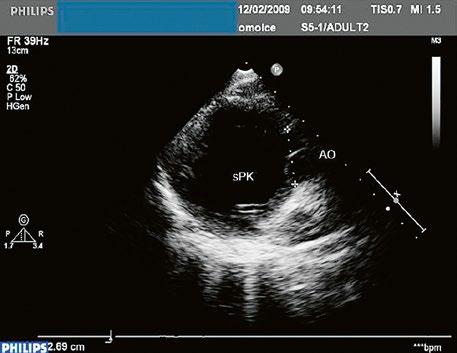

z Defekt síňového septa typu secundum: 70 % všech komunikací na úrovni síní, v místě fossa ovalis, s možnou extenzí ke stěnám levé síně (Obr. 45.1, Obr. 45.2, Video 45.1, Video 45.2).

z Defekt síňového septa typu sinus venosus superior: 9 %, v místě vústění horní duté žíly (HDŽ), která na defekt nasedá, téměř vždy je spojen s parciálním anomálním návratem pravostranných plicních žil do HDŽ nebo do pravé síně (kap. 45.18 Anomální návrat plicních žil (Obr. 45.3, Obr. 45.4, Video 45.3, Video 45.4).

Obr. 45.2 Defekt septa síní typu II v TEE

AO – aorta, ASD – defekt septa síní typu secundum označen šipkou, zelenými křížky je označen malý přední rim k aortě, LS – levá síň, PS – pravá síň